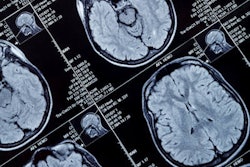

A conventional morphological contrast-enhanced 3-tesla MR image of a brain tumor (left) versus protein measurement using 7-tesla MRI (right). Images courtesy of Dr. Daniel Paech and European Radiology."Malignant gliomas respond very diversely to treatment," explained lead author Dr. Daniel Paech, from the division of radiology at the German Cancer Research Center (DKFZ), in a statement. "In some of the cases, postoperative radiotherapy and chemotherapy are more effective than in others. And whether the tumor has, in fact, responded to treatment cannot be told before the first follow-up care exam six weeks after treatment ends."